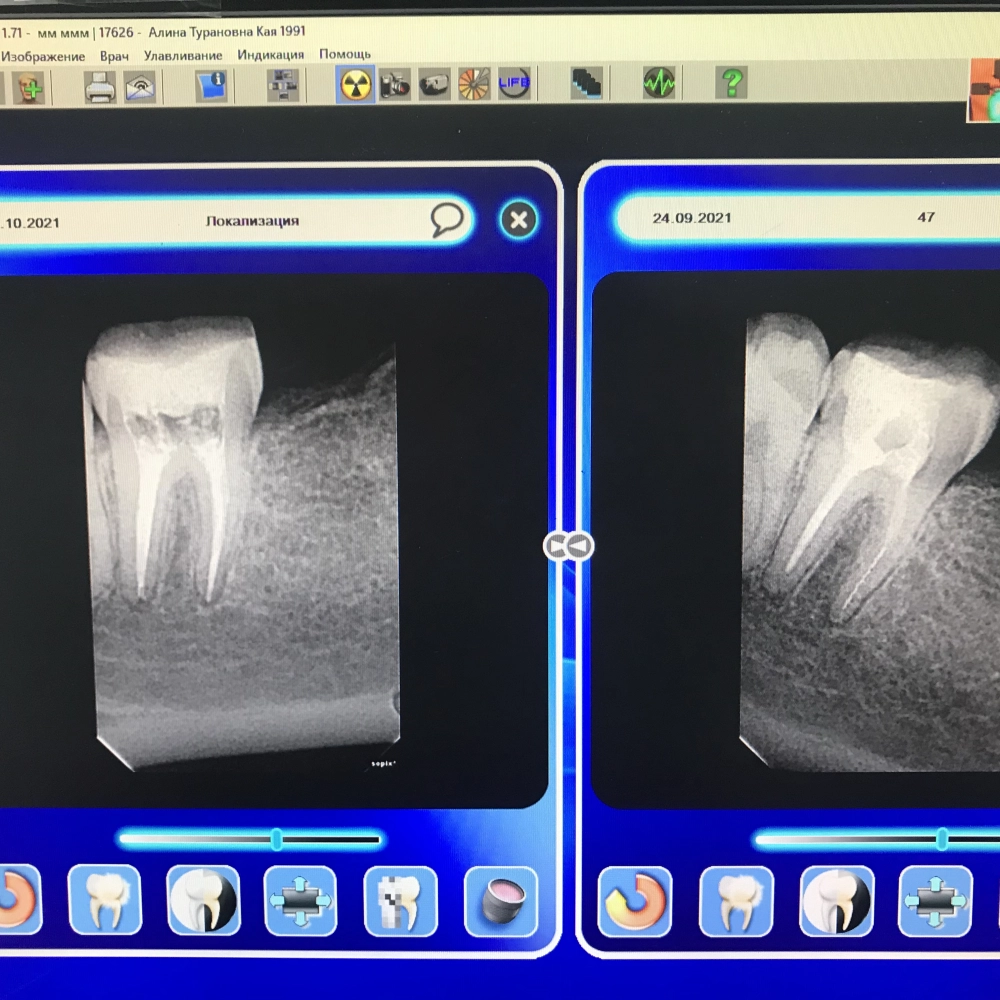

перелечивание зуба

До

После

перелечивание зубов